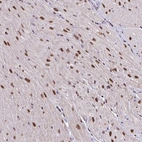

Immunohistochemical staining of human heart muscle shows strong nuclear positivity in myocytes.